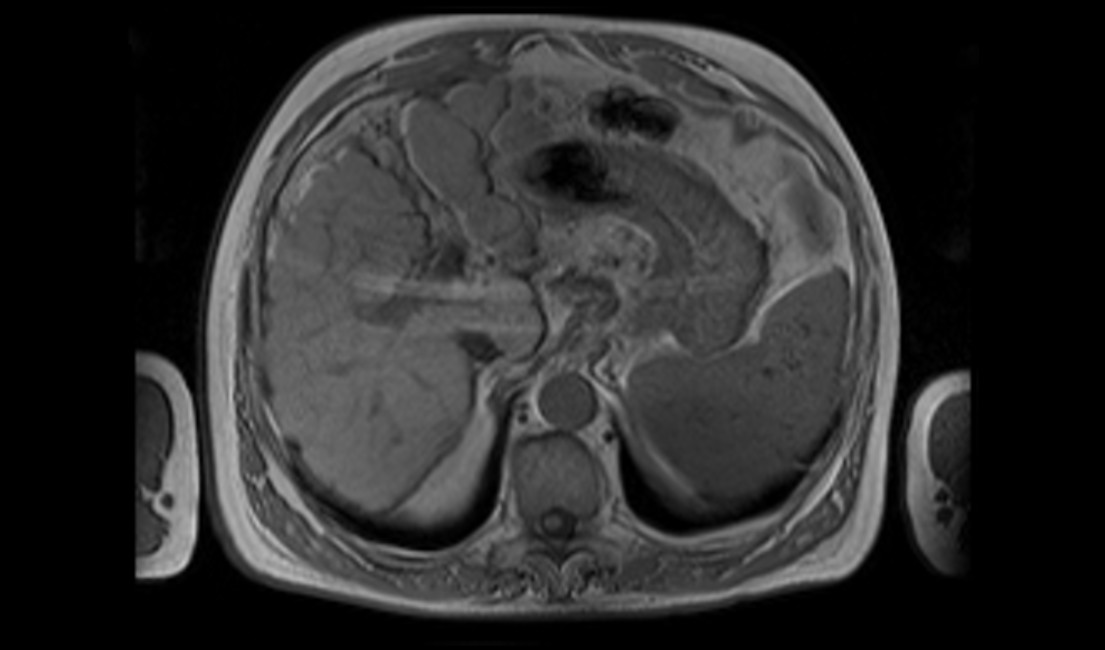

Boricic, Ivan